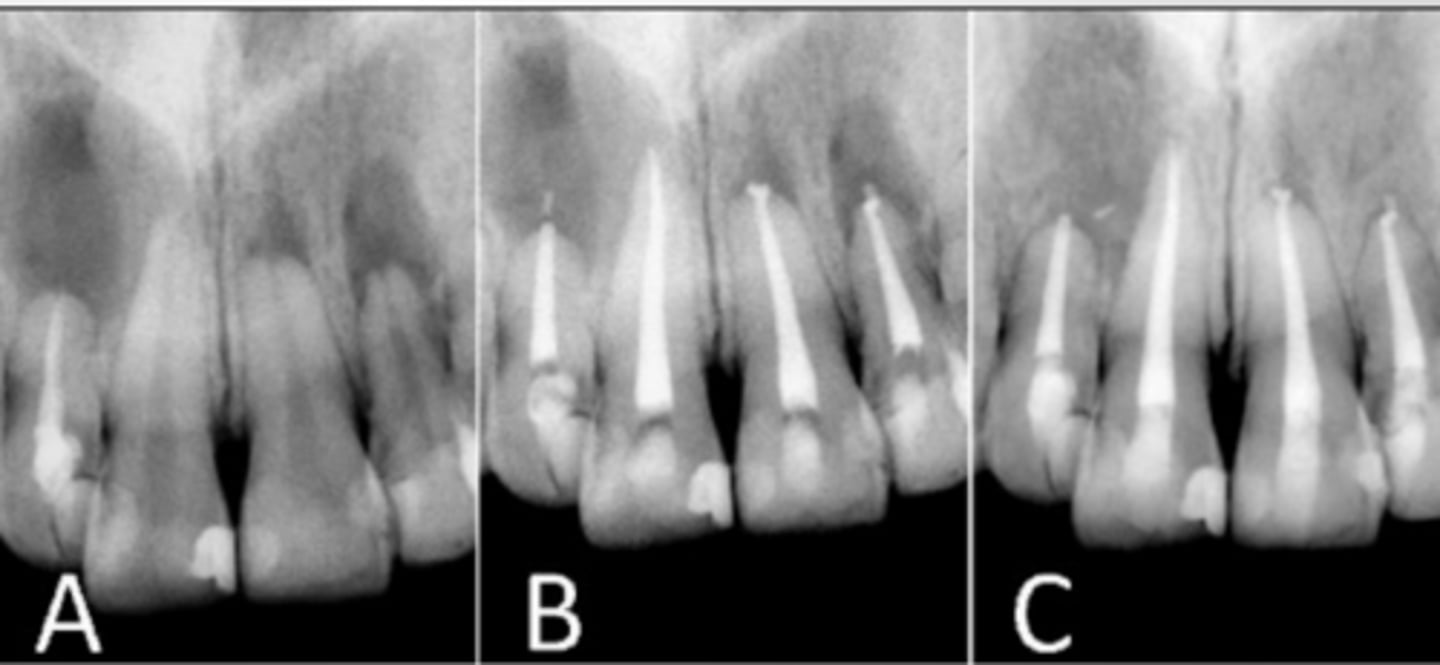

Radiographic View of Pulp, Pulp chamber, and pulp horn